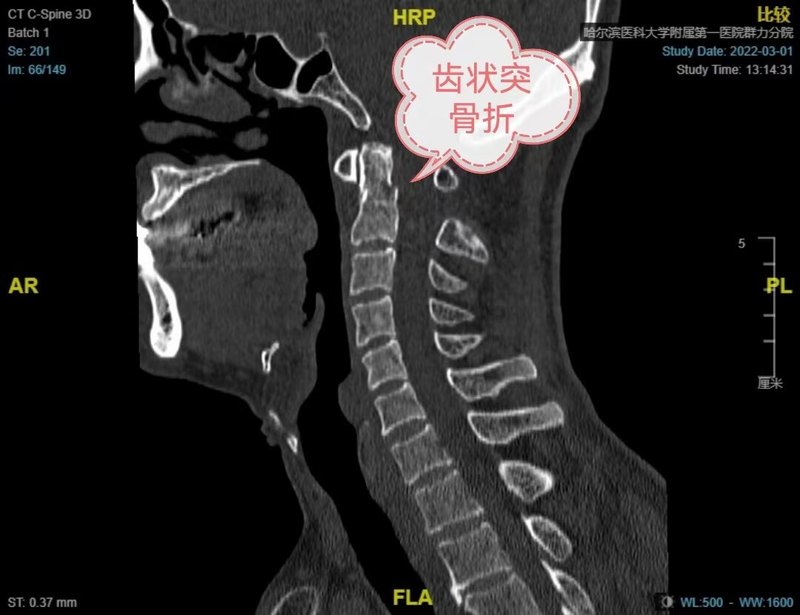

上颈椎骨折经典病例

患者刘先生(化名)从高处坠落后颈部疼痛,诊断齿状突Ⅱ型骨折,属于不稳定骨折,需要手术治疗。颈椎ct显示右侧椎动脉高跨,椎弓根狭小,枢椎椎弓根螺钉置入有极大的椎动脉损伤概率。采用枢椎椎板螺钉技术代替椎弓根螺钉技术,重建上颈椎稳定性,骨折对位对线良好。术后次日离床活动,并顺利康复出院。